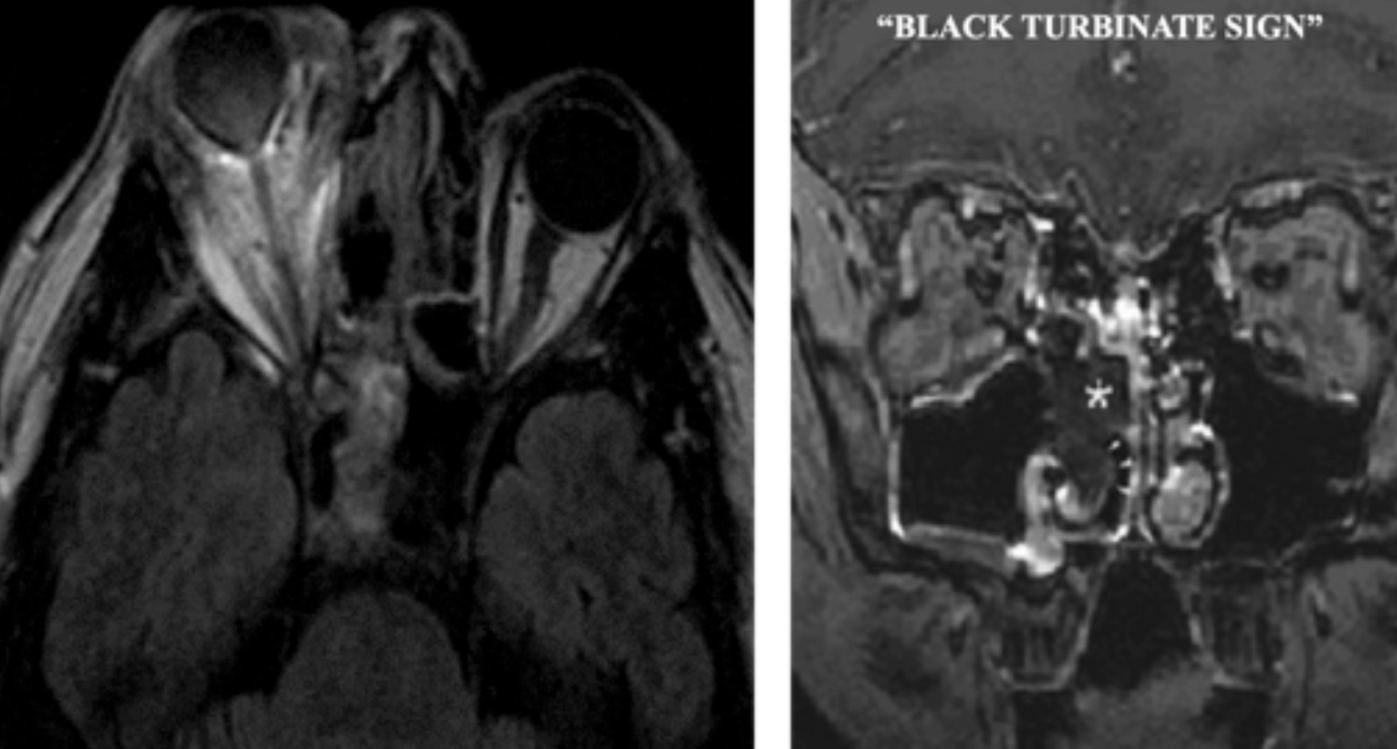

Imaging:

- MRI: “Black turbinate sign” (devitalized tissue in sinuses)

- CT: Reverse halo sign in pulmonary disease

Rhinocerebral Mucormycosis:

- Most common form in diabetic patients

- Begins with sinusitis, facial pain

- Rapid progression with necrotic eschar (black eschar = late finding)

- Orbital involvement: Proptosis, vision loss

- Cavernous sinus thrombosis

- CNS extension: High mortality